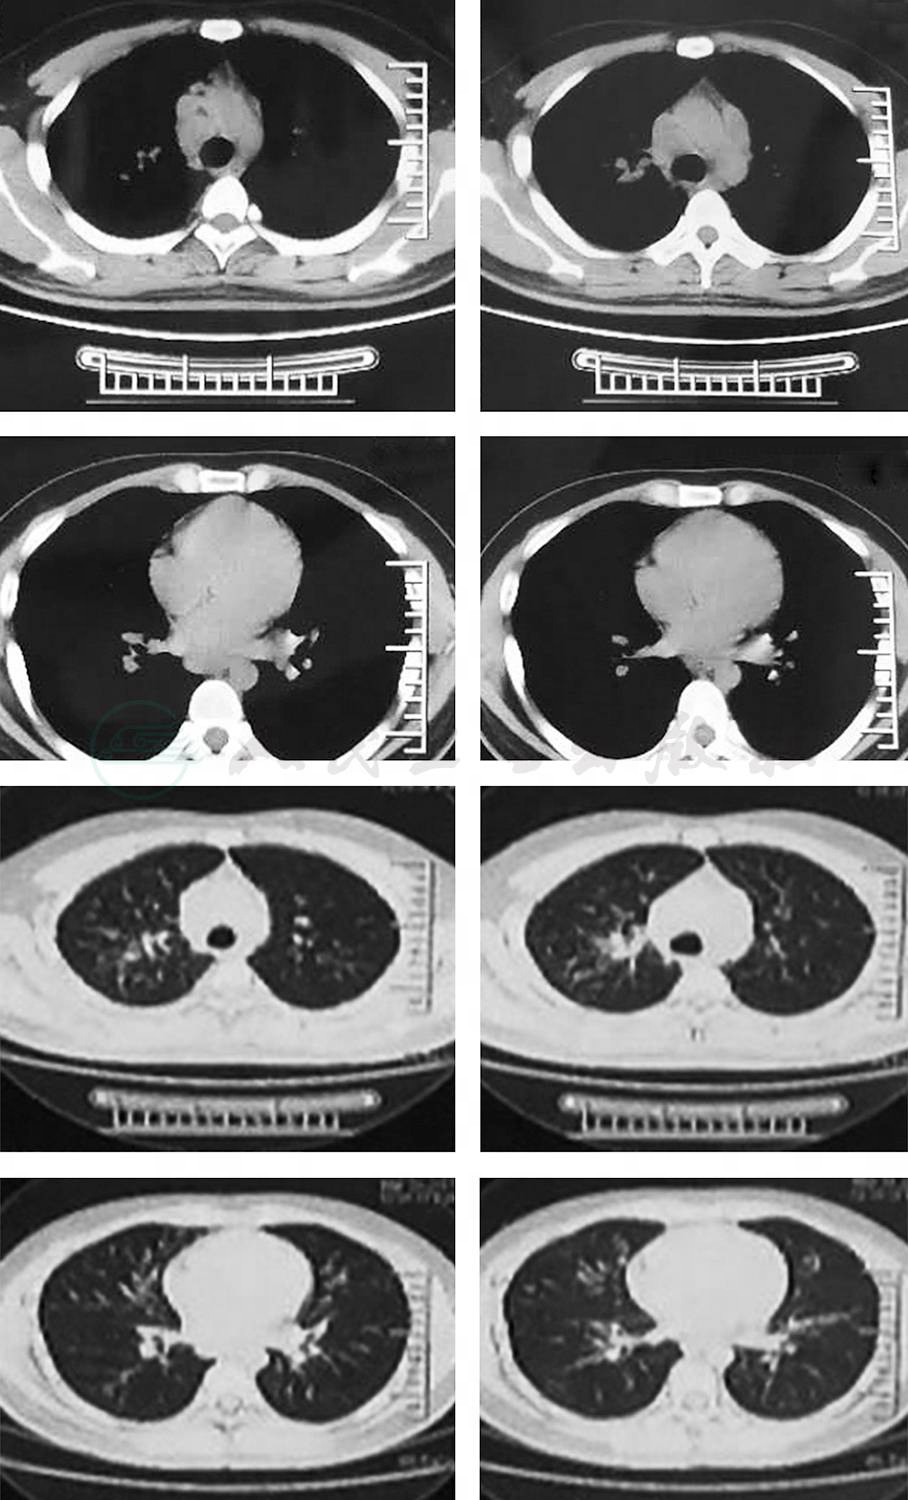

2017年3月患者发现双侧颈部和锁骨上淋巴结肿大,伴胸痛,疼痛部位不固定,多为侧胸部疼痛,偶有前胸部疼痛,为阵发性针刺样,每次持续数十秒至一分钟自行缓解。无咳嗽、咳痰,无畏寒、发热,无盗汗,无呼吸困难等不适。2017年3月30日患者到当地医院就诊,体格检查发现双侧颈前、颈后、锁骨上多个肿大淋巴结,较大者如蚕豆大小;胸部CT示两上肺结节及斑片影,纵隔及双侧肺门淋巴结肿大;T-SPOT阴性;锁骨上淋巴结针吸活检病理示肉芽肿性炎;支气管镜检查示右中间支气管和右中叶支气管黏膜凹凸不平,考虑支气管内膜结核可能。对症治疗后好转出院,具体用药不详,未予抗结核治疗,出院后患者时有胸部隐痛感。2018年2月患者出现胸闷、气促感,活动后气促明显,步行800~1000m及上楼梯至2~3楼即感气促不适。伴口干及大量饮水,24h尿量8000~9000ml。偶有头晕,无头痛,无畏寒、发热,无盗汗,无咳嗽、咳痰等不适。2018年7月31日再次到当地医院就诊,行胸部CT示,与2017年3月对比,双肺结节及斑片影较前明显增多,但纵隔和双肺门淋巴结较前缩小。

①肺部CT:双侧肺门及纵隔淋巴结肿大,伴肺内结节状,片状阴影;②支气管镜黏膜活检:非干酪坏死性肉芽肿性炎症,抗酸染色阴性;③血清ACE活性增高;④T-SPOT和PPD皮试阴性;⑤BALF中淋巴细胞>10%;⑥24h尿钙18.16mmol/24h↑;⑦脾脏多发结节和垂体结节增粗。

该患者服用泼尼松2个月后复查,肺内病灶明显吸收。

3.辅助检查

①肺部CT:双侧肺门及纵隔淋巴结肿大,伴肺内结节状、片状阴影;②支气管镜黏膜活检:非干酪坏死性肉芽肿性炎症,抗酸染色阴性;③血清ACE活性增高;④T-SPOT和PPD皮试阴性;⑤BALF中淋巴细胞>10%;⑥24h尿钙18.16mmol/24h↑;⑦脾脏多发结节和垂体结节增粗。

放射科:临床及影像学表现符合结节病,Ⅰ期和Ⅱ期结节病可以有对称性肺门纵隔淋巴结肿大,Ⅲ期结节病肺内出现结节和纤维化病变,纵隔淋巴结消失,Ⅳ期结节病出现蜂窝肺,并且结节病非常容易累及颅内垂体,导致尿崩症,该患者完全符合。